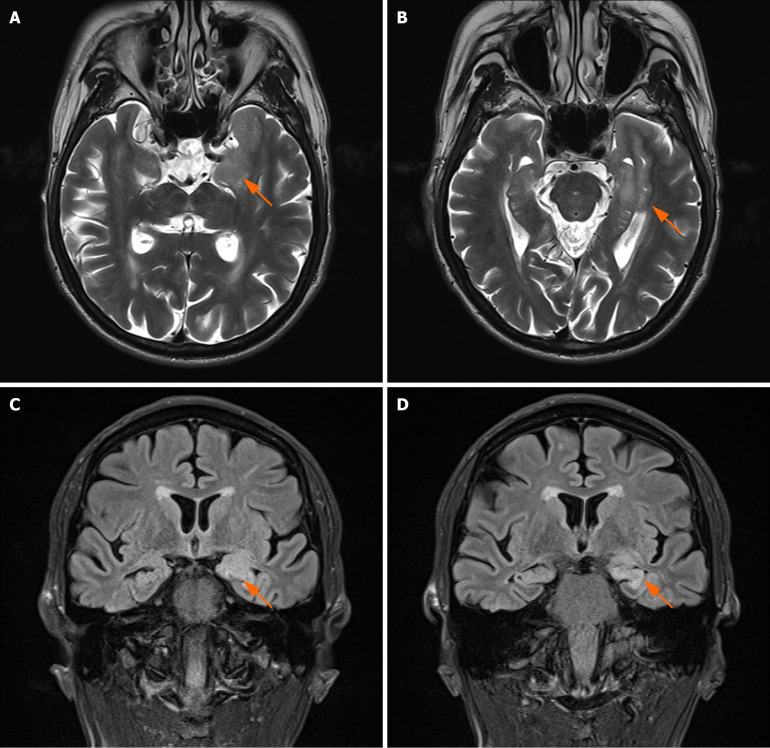

Case summary: This report describes a patient with rapid cognitive impairment, diagnosed with anti-LGI1 antibody-mediated AE and aMCI, and treated at Peking University Shenzhen Hospital in March 2023. The patient was hospitalized with acute memory decline for more than 3 months. Both the cerebrospinal fluid and serum were positive for anti-LGI1 antibodies, biomarkers of AD coexisting in the patient's cerebrospinal fluid. Following combination treatment with immunoglobulin therapy and glucocorticoid, plus inhibition of acetylcholinesterase, the patient's cognitive function significantly improved. Throughout the 3-month follow-up period, a sustained improvement in cognitive function was observed. The results of serum anti-LGI1 antibody were negative.